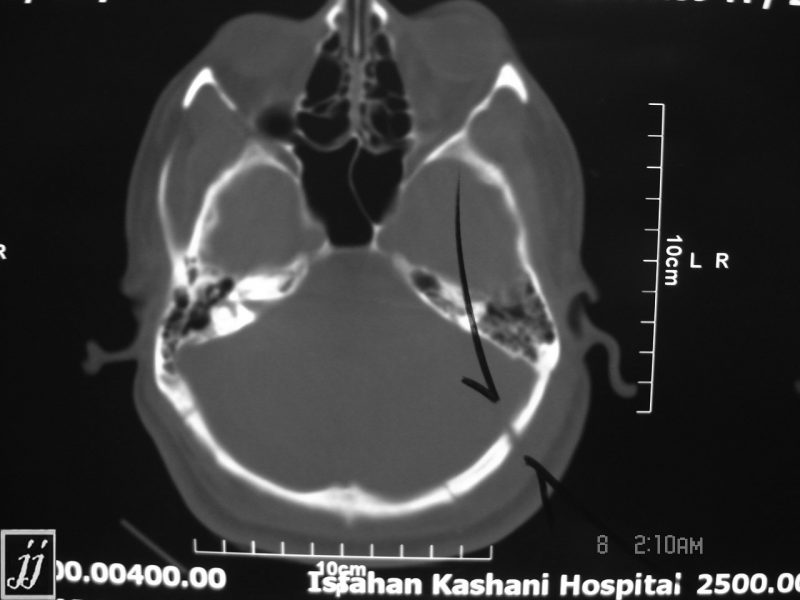

CT of the brain in a 23yearold male with occipital bone fractures. He Crushing Injury Of The Occipital Bone Is Often Fatal Aquired instability is treated with observation or occipitocervical fusion depending on the presence of neurologic deficits. Severe head injuries require immediate medical ttention because there's a risk of serious brain damage. Massive forces literally crush the head causing fractures of the facial skeleton, calvarium and skull base. Neurological injury from aod can be devastating and may often lead to sudden.. Crushing Injury Of The Occipital Bone Is Often Fatal.

Radioogle Brain occipital bone fracture, subdural hematoma (6) Crushing Injury Of The Occipital Bone Is Often Fatal Aquired instability is treated with observation or occipitocervical fusion depending on the presence of neurologic deficits. Basal skull fractures are most frequently diagnosed by clinical findings, making clinical assessment skills critical. Severe head injuries require immediate medical ttention because there's a risk of serious brain damage. Ct may reveal suspicious fluid collections. Massive forces literally crush the head causing fractures. Crushing Injury Of The Occipital Bone Is Often Fatal.